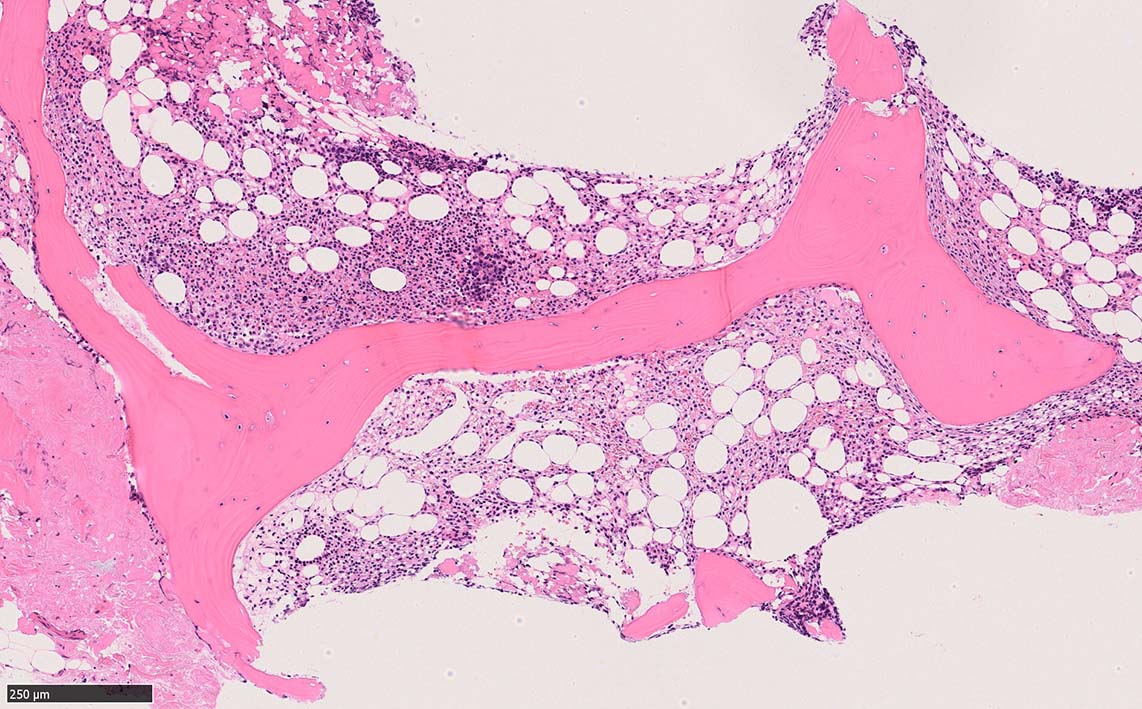

骨髄生検

bone marrow trephine biopsy: dry tapのため骨髄生検が行われる. cellularityは40-80%とhypercellular marrow. 流れのある細胞配列は線維化を疑わせる.